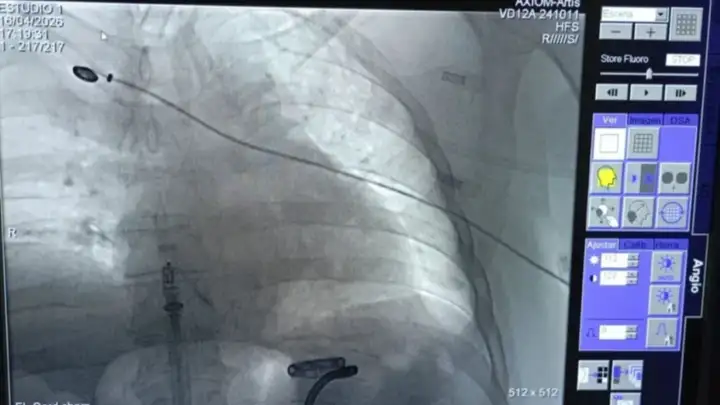

En 40 minutos le implantaron el marcapasos más chico del mundo. Foto NoticiasNet.

En apenas 40 minutos y con una tecnología que parece salida del futuro, un paciente volvió a tener una vida normal tras recibir un marcapasos de última generación en la Clínica Viedma, en un procedimiento que marca un antes y un después en la cardiología de Río Negro.

El implante fue realizado por el equipo del Servicio de Electrofisiología de la Unidad de Cardiología, encabezado por el médico Martín Calvelo, con la supervisión del especialista Ariel Estévez, proctor de la empresa Medtronic, líder mundial en tecnología médica. No se trató de una intervención más: fue la llegada concreta de un dispositivo revolucionario que cambia las reglas del juego.

Se trata del Micra AV2, un marcapasos diminuto, apenas dos centímetros de largo y dos gramos de peso, que es hasta diez veces más pequeño que los modelos tradicionales. Pero no es solo cuestión de tamaño. Este dispositivo elimina los cables, uno de los puntos más críticos de los marcapasos convencionales, y con eso reduce de manera drástica el riesgo de infecciones y complicaciones.

Además, el procedimiento es mínimamente invasivo. A diferencia de las cirugías tradicionales, no requiere la creación del clásico “bolsillo” bajo la piel donde se alojan los equipos antiguos. Todo se implanta directamente en el corazón mediante una técnica precisa y controlada. Menos intervención, menos riesgo, más recuperación.